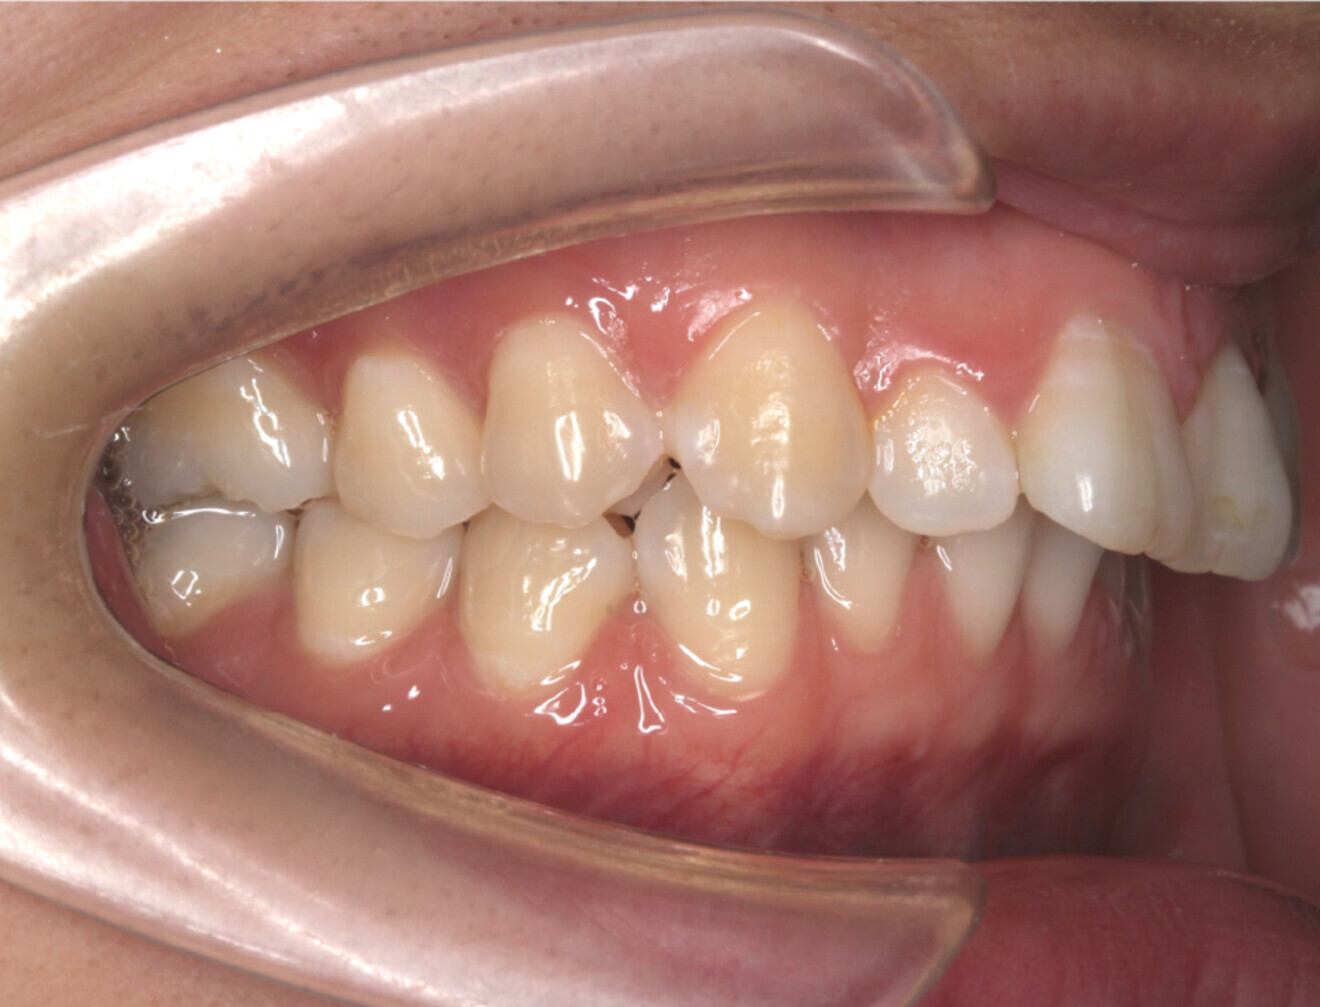

Fig. 1d: Lateral intra-oral view.